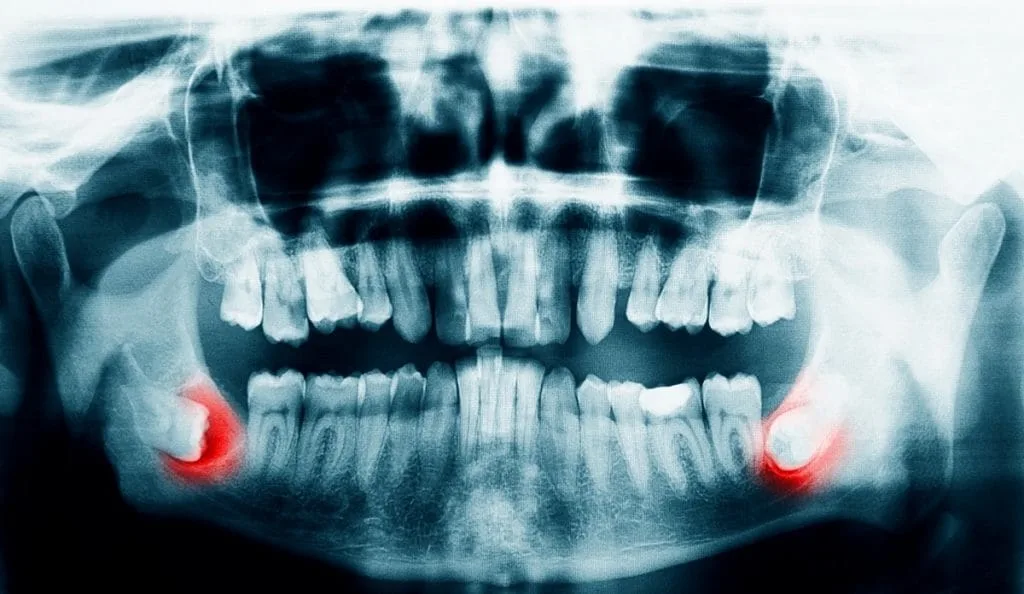

A dental specialist will determine which type of extraction you need. They will take the necessary steps, such as dental X‑rays and a thorough examination of your teeth and mouth, to make the right decision.Although some teeth that appear suitable for a simple extraction may still require a surgical approach, several factors are considered when deciding whether a patient qualifies for surgical extraction, including:– The tooth is impacted (partially or completely trapped in the bone or gum), as is common with wisdom teeth – The tooth is broken at or below the gum line – The roots are curved, long, or unusually shaped – The tooth is ankylosed (fused to the bone) – There is dense surrounding bone or limited access to the area – There are existing restorations (like crowns or bridges) attached to the tooth – The patient’s medical condition requires a more controlled surgical settingIn general, a simple tooth extraction is recommended whenever possible because it is easier to perform and is associated with fewer side effects than surgical extraction.See also: Open Bite Correction – Do You Really Need It?